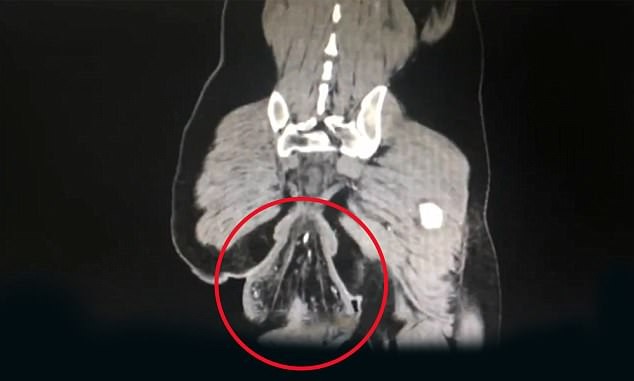

▲蹲馬桶30分鐘後,少年一站起來多了條「尾巴」。(圖/翻攝看看新聞,下同。)

根據《看看新聞》報導,廣州中山大學附屬第六醫院的醫生表示,少年的病況為「直腸脫垂」,也就是俗稱的「脫肛」,發生比率不低,但是像這樣子拉出一顆「排球」的嚴重情況卻很少見,「他已經完全不能自行復位了,而且直腸壁還有發黑的瘀血。」

▼少年直腸脫垂,還拉出一顆排球。